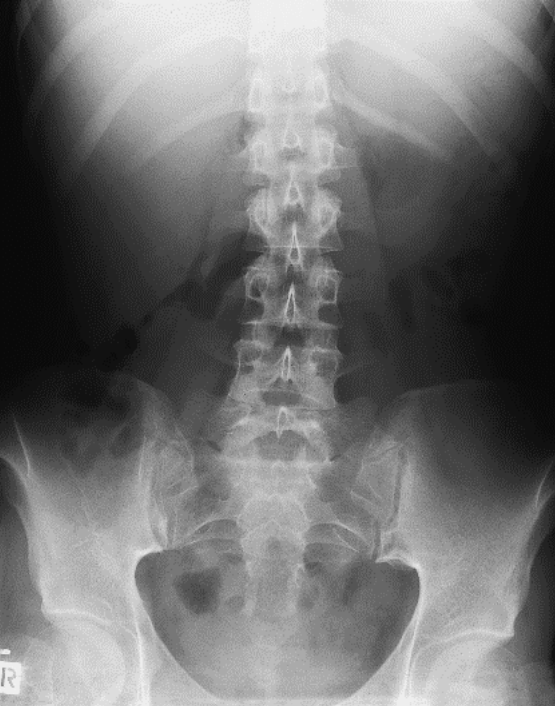

Które badanie zostało zarejestrowane na przedstawionym radiogramie?

Ilustracja do pytania 21

A. Jamy brzusznej wykonane poziomą wiązką promieniowania.

B. Płuc wykonane metodą Przybylskiego.

C. Układu moczowego z użyciem środka kontrastującego.

D. Dróg żółciowych metodą cholangiografii śródoperacyjnej.